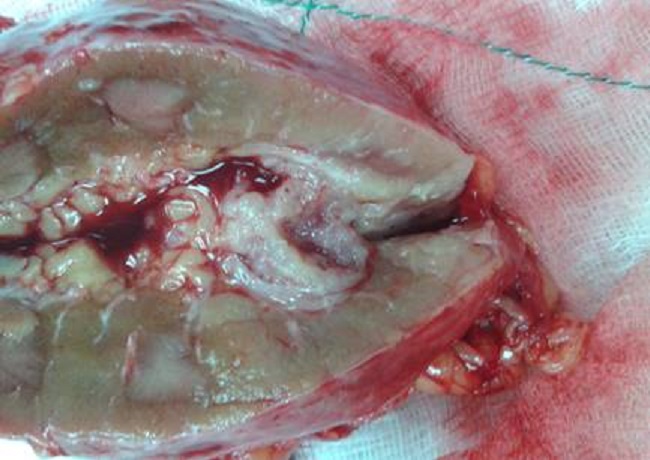

Se practicó nefrourectomía derecha, se extirpó un tumor de 2 cm de bordes irregulares en la unión ureteropélvica, no adenopatías, no invasión de vísceras vecinas sin signos de metástasis. El paciente es referido al departamento de Oncología para su seguimiento al igual que al servicio de Urología con el diagnóstico histológico de carcinoma urotelial (Figuras 1 y 2).